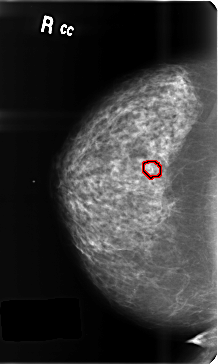

B_3459_1.RIGHT_CC

RIGHT_CC LINES 4728 PIXELS_PER_LINE 2832 BITS_PER_PIXEL 12 RESOLUTION 50 OVERLAY

FILE: B_3459_1.RIGHT_CC.OVERLAY

TOTAL_ABNORMALITIES 1

ABNORMALITY 1

LESION_TYPE CALCIFICATION TYPE PLEOMORPHIC DISTRIBUTION CLUSTERED

ASSESSMENT 4

SUBTLETY 4

PATHOLOGY BENIGN

TOTAL_OUTLINES 1